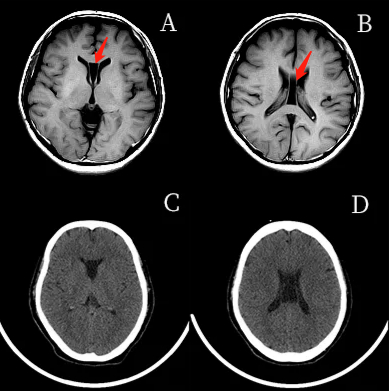

第五脑室真不是透明隔腔不能再错了

透明隔间腔 [第五脑室](实箭),vergae腔 [第六脑室](虚箭)